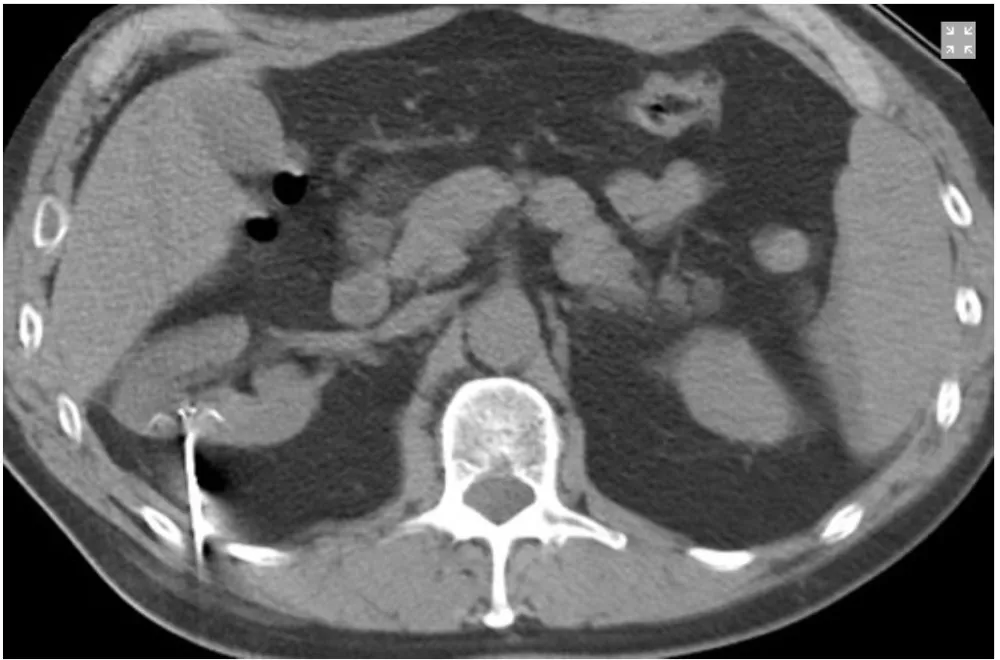

Múltiplos tumores renais